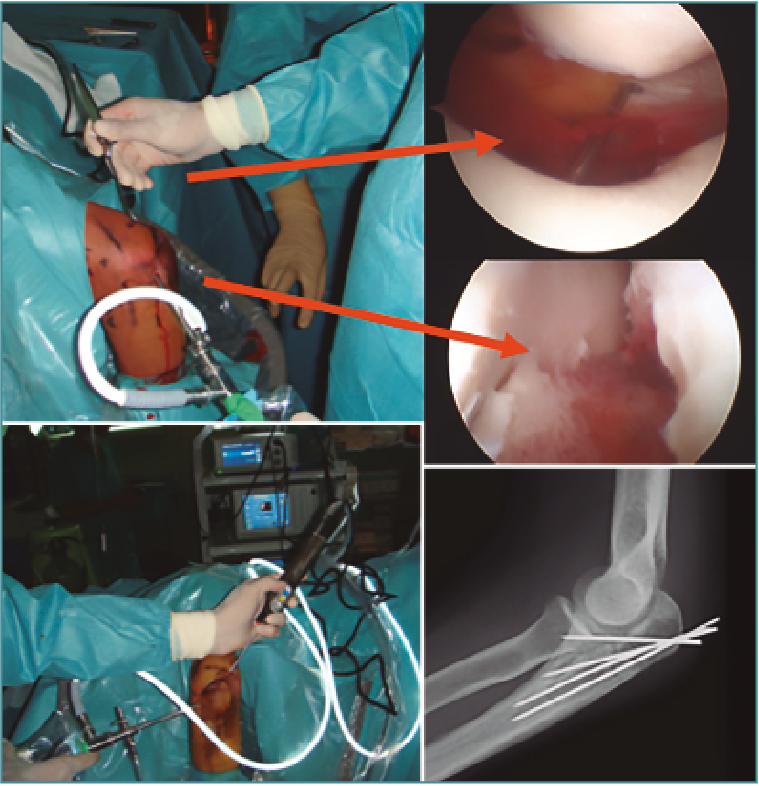

La reducción abierta y la fijación interna es el tratamiento recomendado para las fracturas de tipo III debido a la alta incidencia de inestabilidad asociada con estos grandes fragmentos de fractura. La intervención quirúrgica también se recomienda para cualquier fractura del proceso coronoide que interfiera con el movimiento articular(4). Si hay un alto grado de conminución de la fractura coronoide y no es posible la fijación interna, se indica la colocación de fijación externa para mantener la congruencia de la articulación del codo durante la cicatrización del tejido blando y óseo. Cuando hay presente un gran fragmento de fractura de un proceso coroideo, sin embargo, puede visualizarse y asegurarse de forma efectiva utilizando técnicas artroscópicas. Se puede fijar con AK o bien insertar una guía de ligamento cruzado anterior tibial a través del portal medial anterior y se usa para manipular y reducir anatómicamente el fragmento de la fractura. A continuación, taladramos el olécranon desde fuera hacia la articulación controlado con visión directa hasta atravesar la fractura de la coronoides. Luego, se puede usar distintas técnicas, desde una lazada con sutura de alta resistencia (Figura 7) hasta un pequeño tornillo canulado para asegurar el fragmento de fractura del proceso coronoide y ayudar a restablecer la estabilidad de la articulación(5).

Figura 7. Fractura de coronoides asistida por artroscopia con sistema de lazada.

Las fracturas de cabeza radial desplazadas en 2 partes a menudo son susceptibles de evaluación y tratamiento artroscópico. La mayoría de los autores creen que, si el fragmento desplazado bloquea la rotación del antebrazo, está indicada la intervención quirúrgica. La visualización a través del portal medial anterior proximal permite evaluar no solo la incongruencia articular, sino también la estabilidad del fragmento de fractura a través de un rango de rotación del antebrazo(7). Cualquier bloqueo óseo a la rotación también se identifica fácilmente. Tras lavar la articulación del codo con suero y desbridar los coágulos, se aprecia de forma clara el tipo de fractura y el número de fragmentos óseos. A continuación, se puede utilizar una AK de 1,8-2,2 mm a modo de joystick para permitir la manipulación y reducción de algunas fracturas de cabeza radial de 2 partes. Después de la reducción se puede utilizar un tornillo canulado de tipo Herbert o similar para asegurar la fijación (Figura 8). Para este procedimiento, es obligatorio conocer a fondo la anatomía neurovascular y la ubicación del portal. Los tornillos pueden colocarse percutáneamente a través de los portales establecidos o nuevas incisiones exclusivas para introducirlos en la dirección óptima. Cada fractura es diferente y puede requerir diferentes ángulos de inserción del tornillo. Este tornillo autocomprimible proporciona buena estabilidad y permite un movimiento temprano. Este implante también se puede enterrar completamente debajo del borde articular del cartílago de la cabeza radial, evitando así la obstrucción del dispositivo en la articulación radiocubital proximal.

Figura 8. Fractura de la cabeza radial asistida por artroscopia.